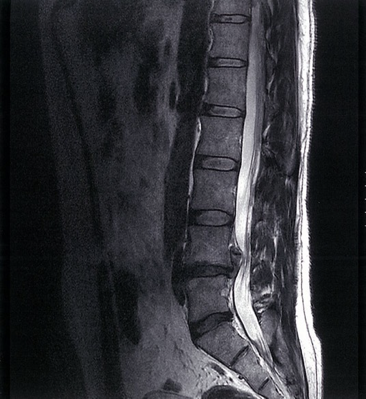

Degenerative disk disease with disk extrusion

MRI lumbar spine (T2-weighted; sagittal plane)

Hypointense degenerated disks at L4–5 and L5–S1 are accompanied by disk space narrowing. A disk extrusion at L4–5 has migrated superiorly behind the L4 vertebral body and narrows the thecal sac.